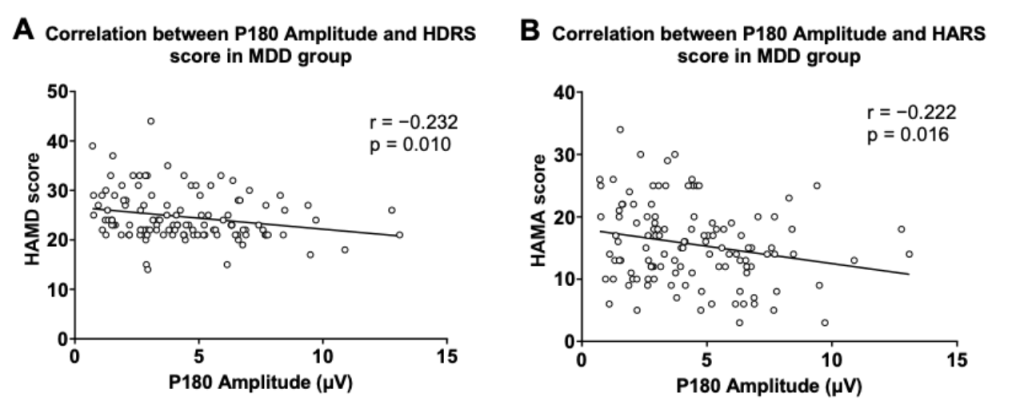

圖2. P180波幅與抑郁及焦慮癥狀得分的關(guān)系

圖1分別顯示了健康對照組與患者組的TMS誘發(fā)腦電的蝴蝶圖。研究結(jié)果顯示,抑郁癥患者P180波幅顯著低于健康對照人群。在抑郁癥患者中,P180波幅與抑郁、焦慮癥狀得分呈顯著負(fù)相關(guān);P30波幅與RBANS視覺空間/結(jié)構(gòu)得分和總分呈顯著負(fù)相關(guān)。

多元回歸分析表明,P180波幅能負(fù)向預(yù)測患者的抑郁及焦慮癥狀;P30波幅、發(fā)病年齡和教育程度能負(fù)向預(yù)測患者的認(rèn)知功能。